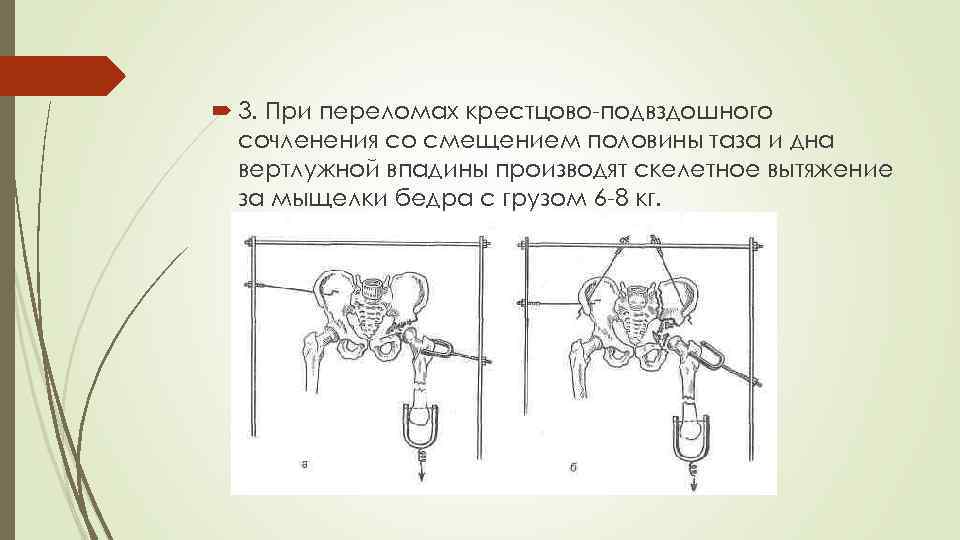

3. При переломах крестцово-подвздошного сочленения со смещением половины таза и дна вертлужной впадины производят скелетное вытяжение за мыщелки бедра с грузом 6 -8 кг.